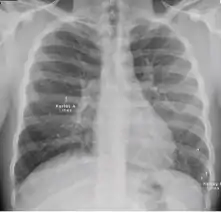

Radiology (X-rays) is used in the diagnosis of tuberculosis. Abnormalities on chest radiographs may be suggestive of, but are never diagnostic of TB, but can be used to rule out pulmonary TB.

Chest X-ray

Tuberculosis creates cavities visible in x-rays like this one in the patient's right upper lobe.

A posterior-anterior (PA) chest X-ray is the standard view used; other views (lateral or lordotic) or CT scans may be necessary.

In active pulmonary TB, infiltrates or consolidations and/or cavities are often seen in the upper lungs with or without mediastinal or hilar lymphadenopathy.[1] However, lesions may appear anywhere in the lungs. In HIV and other immunosuppressed persons, any abnormality may indicate TB or the chest X-ray may even appear entirely normal.[1]